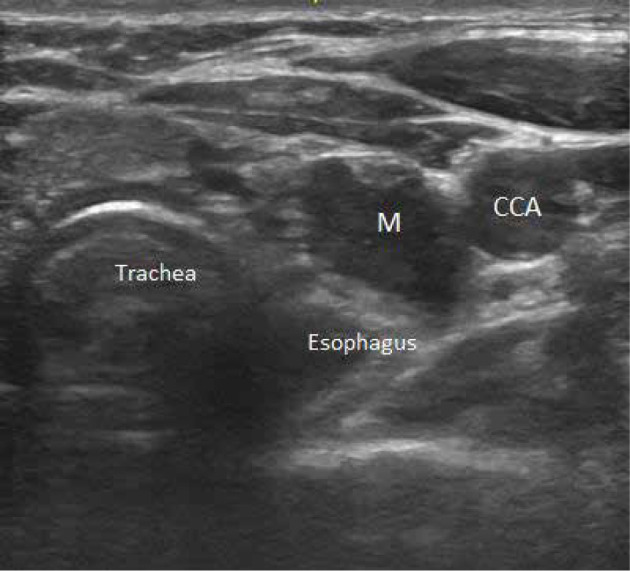

Purpose: Primary hyperparathyroidism is mainly caused by parathyroid adenomas. Preoperative imaging can be performed using different imaging modalities, e.g. ultrasound (US), radionuclide scanning, magnetic resonance imaging, and computed tomography, often used in combination. Currently, US-guided blue dyes, especially methylene blue (MB) injection, are used to identify parathyroid tumours.

Material and methods: This was a retrospective study of 228 patients. Preoperative ultrasound, scintigraphy, and bio-chemistry were performed on all patients, and fine-needle aspiration procedures were performed on suspected patients. Using preoperative US-G injection with MB dye, target tumours were injected in all cases.

Results: A total of 163 patients were female and 65 were male. The mean age was 42.5 years. US was positive in 203 (89%) cases, 25 (11%) were negative, and all had a positive sestamibi scan (100%). US-G needle injections with MB dye of target tumours were successful in all cases. The average diameter of the lesions was 18 mm. All had positive intraoperative identification of parathyroid adenoma and MB staining (100% accuracy, 100% sensitivity, and 100% specificity). Operating time (min ± SD) was 22.7 ± 11.5 minutes, and the success rate was 100%. All were parathyroid adenomas histologically. Intraoperative parathormone hormone decreased in all patients. In postoperative follow-up, all were normocalcaemic with no local or systemic complications.

Conclusions: Localisation of small parathyroid adenomas by US-guided blue dye injection is a safe, simple, and useful tool when performing parathyroidectomy with no complications.